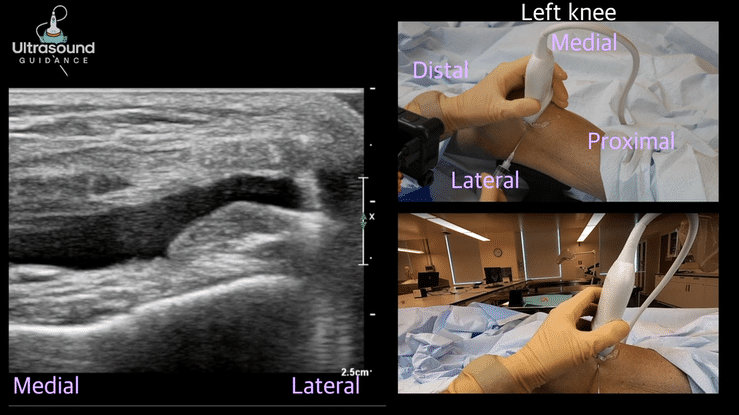

| A1 Pulley Release Procedure | Medial Knee | Knobology |

| Achilles Tendon Needle Tenotomy/Injection/Tendon Scraping | Lateral Knee | Artifacts |

| Medial Meniscus Injection | ||

| Medial Subpatellar Knee Injection | ||